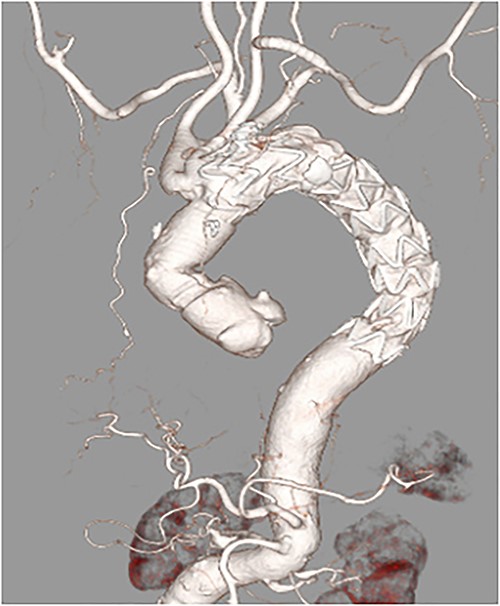

After primary aortography was performed using a 5-F pigtail catheter, the landing zones were marked; the introducer was inserted; and the endoprosthesis was tracked and centred over the aneurysm under fluoroscopic guidance, deployed and subsequently ballooned in Zone 2. Angiography revealed a type 1 endoleak; therefore, inflation with a trilobe balloon was performed. Two 8 × 20 cm coils (Interlock™, Boston Scientific, Marlborough, Massachusetts) were introduced through the left subclavian artery into the aneurysms for embolization. The final angiogram showed a slight leak in the aneurysm; however, the blood flow was determined to be from the left subclavian artery, and the procedure was terminated. Although contrast-enhanced CT performed on postoperative Day 8 showed a type 4 endoleak (Fig. 2). The postoperative course was uneventful, and she was discharged on Day 15.

Postoperative enhanced-computed tomography findings. There were no problematic findings, although a slight type 4 endoleak was present.